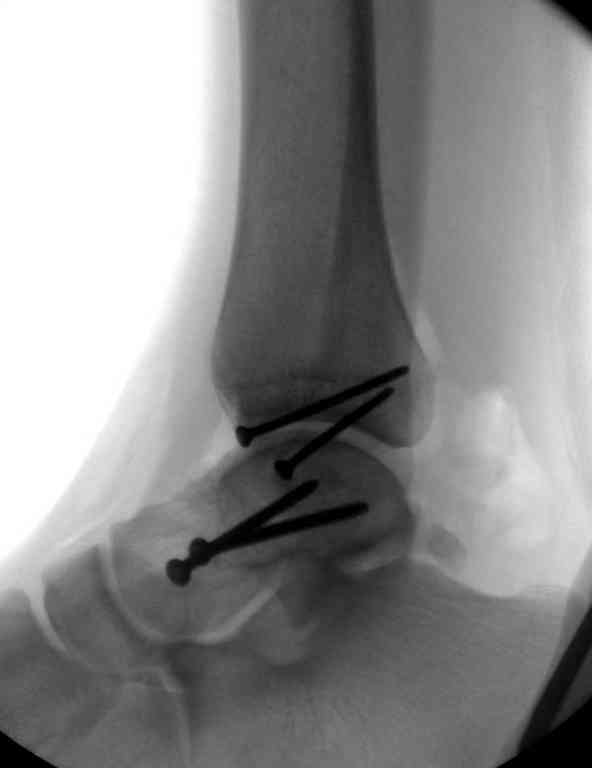

Второй случай прооперирован вчера.

10 дней назад поступил с открытым повреждением медиальной лодыжки и переломо вывихом таранной кости. Ургентно сделана репозиция с наложением наружного фиксатора + Irrigation&Debridment.

Во время репозиции выявили повреждение заднего сухожилия м. тибиалис и задней большеберцовой артерии. Медиальную рану удалось закрыть частично и установлен вакуум.

Дважды провели Irrigation&Debridment с заменой вакуума.

Вчера провели фиксацию.

Из-за многооскольчатости дистальной части малоберцовой, где невозможно было провести фиксацию шурупами, перелом зафиксирован подпирающей пластиной, которая должна служить дополнением отсутствующей дистальной части малоберцовой (lateral cortex substitute).

Для стабильности два шурупа на синдесмоз.

Медиальную рану с приближенными краями продолжаем вакуумировать (KCI). Наружный фиксатор оставлен на пару недель, надеюсь, небольшая рана будет гранулировать и закроется без кожной пластики. Фиксация медиальной ложыжки не планируется.